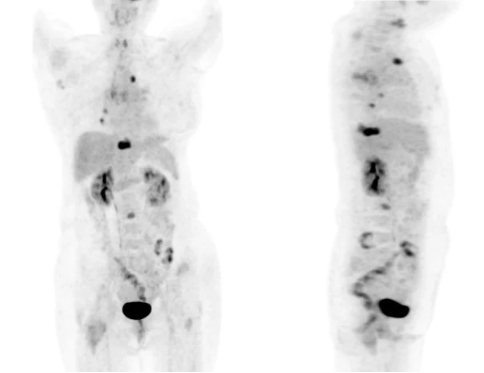

不负众望,PET/CT发现了新的线索——“右侧乳腺外上象限结节,代谢轻度增高”。正是这轻度的代谢增高,给医生提供了明确诊断的新思路,这是一例隐匿性乳腺癌伴肺、骨多发转移。最后病理证实是癌,免疫组化支持乳腺来源。

PET和CT融合后的图像